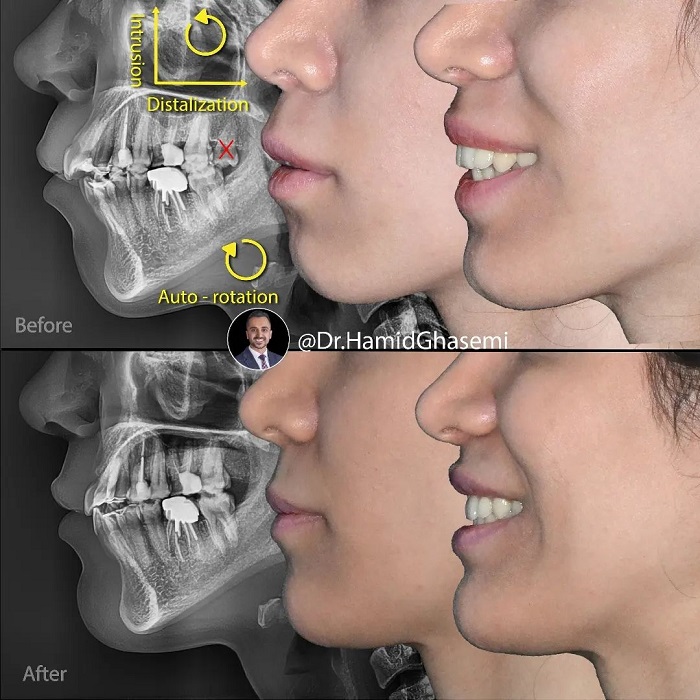

توتال ایمپکشن و توتال دیستالیزیشن بدون جراحی فک در فک بالا و به دنبال آن auto rotation(چرخش فک پایین به دنبال جابجایی فک بالا) مندیبل با استفاده از Tad system (ساخته شده از Double TPA اختصاصی متصل و مينی اسکرو). بیمار با سابقه انجام ارتودنسی ناموفق همراه با کشیدن دندان قدامی در فک پایین و ارجاع بیمار به جراح جهت انجام جراحی ۲ فک بعد از ۲ سال درمان ارتودنسی به امید انجام درمان مجدد بدون جراحی فک به کلینیک بنده مراجعه کردند و خیلی خوشحالم که در انتها به نتیجه دلخواه رسیدند. به تغییرات ایجاد شده در صورت (۱/۳ تحتانی ) و فکین بعد از درمان توجه کنید. ورق بزنید و نظر خودتون رو برامون کامنت کنید. 💪💪💪

🔺️Non surgical orthodontic total impaction and total distalization of maxillary arch followed by auto rotation of lower jaw using Tads system which customized by connected double TPA and mini intra radicular screws. This patient had history of unsuccessful orthodontic treatment with extraction of lower front tooth and both jaw surgery was offered to her by her former orthodontist after almost 2 years orthodontic treatment and she came all the way to our office to plan for non surgical orthodontic re-treatment and im glad that she is happy with result. Take note on significant changes done on overall facial(lower 3rd) and dentition. Slide and comment your opinion… 💪💪💪